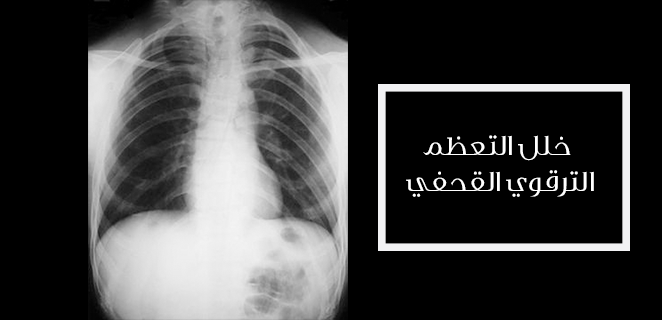

خلل التعظم الترقوي القحفي

هي عقدة خِلْقِيَّة قَدْ تكُون وراثيَة وتتميّز بنمو غِائب أو...